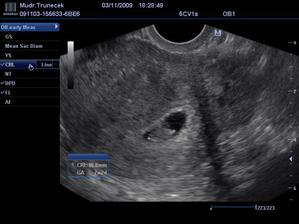

Náš František a jeho mladší sourozenec

Dne 17.10.2009 mamka zjistila, že, ač neplánovaně, budu mít sourozence.TP je zatím 21. 6.2010.